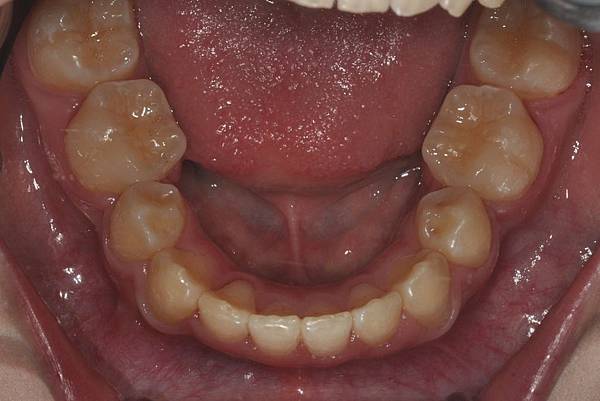

拔牙改善高位虎牙

虎牙妹的女神蛻變之旅~

此案例因為空間不足排列牙齒,

考量到不拔牙將使得牙齒前凸破壞患者原本和諧的側臉。

故上下左右各拔一小臼齒。